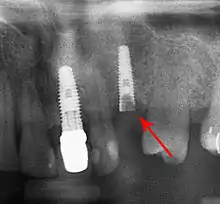

Bone loss (peri-implantitis) on implants over 7 years in a heavy smoker

Fixture show

Cement peri-implantitis

Dental cement under the gingiva causes peri-implantitis and implant failure.

Long-term failures are due to either loss of bone around the tooth and/or gingiva due to peri-implantitis or a mechanical failure of the implant. Because there is no dental enamel on an implant, it does not fail due to cavities like natural teeth. While large-scale, long-term studies are scarce, several systematic reviews estimate the long-term (five to ten years) survival of dental implants at 9398 percent depending on their clinical use.[1][2][3] During initial development of implant retained teeth, all crowns were attached to the teeth with screws, but more recent advancements have allowed placement of crowns on the abutments with dental cement (akin to placing a crown on a tooth). This has created the potential for cement, that escapes from under the crown during cementation to get caught in the gingiva and create a peri-implantitis (see picture below). While the complication can occur, there does not appear to be any additional peri-implantitis in cement-retained crowns compared to screw-retained crowns overall.[68] In compound implants (two stage implants), between the actual implant and the superstructure (abutment) are gaps and cavities into which bacteria can penetrate from the oral cavity. Later these bacteria will return into the adjacent tissue and can cause periimplantitis.